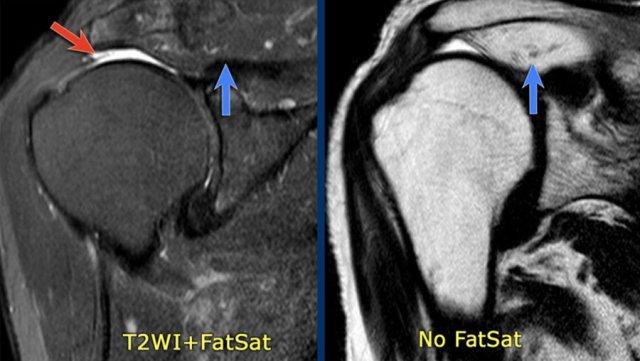

Trên các chuỗi xung có ức chế mỡ, việc đánh giá teo cơ và thay thế mỡ có thể gặp khó khăn.

Hình ảnh

Trên hình ảnh có ức chế mỡ bên trái, có thể nhận định nhầm rằng cơ trên gai bình thường (mũi tên xanh lam).

Tuy nhiên, trên hình ảnh không có ức chế mỡ, có thể thấy rõ tình trạng teo cơ nặng và thay thế mỡ với tín hiệu cao (mũi tên xanh lam).

Mũi tên đỏ chỉ vị trí rách toàn bộ chiều dày của gân cơ trên gai.